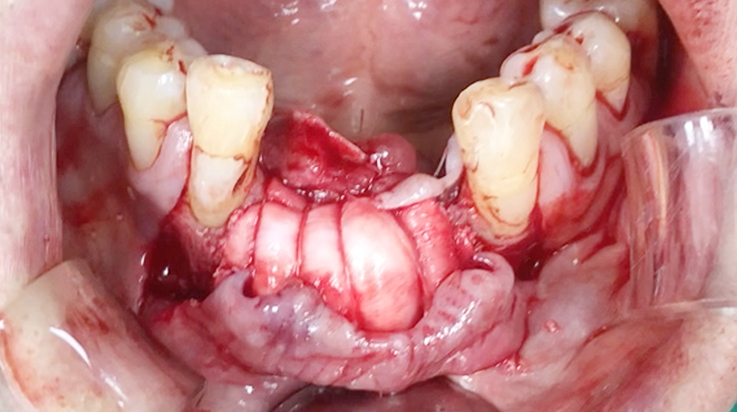

A surgical procedure using resorbable membrane

• A surgical procedure using resorbable membrane 2